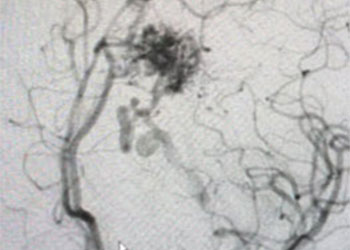

Endovascular:

Hydrocephalus and Brainstem Tumor

Author: Jonathan L. Brisman M.D., F.A.C.S., Read More!

Carotid Cavernous Fistula (CCF) Study

Carotid Cavernous Fistula (CCF)

CME:

Symptomatic Near-Occlusion of the Carotid Artery

Direct Carotid Cavernous Fistula (CCF)